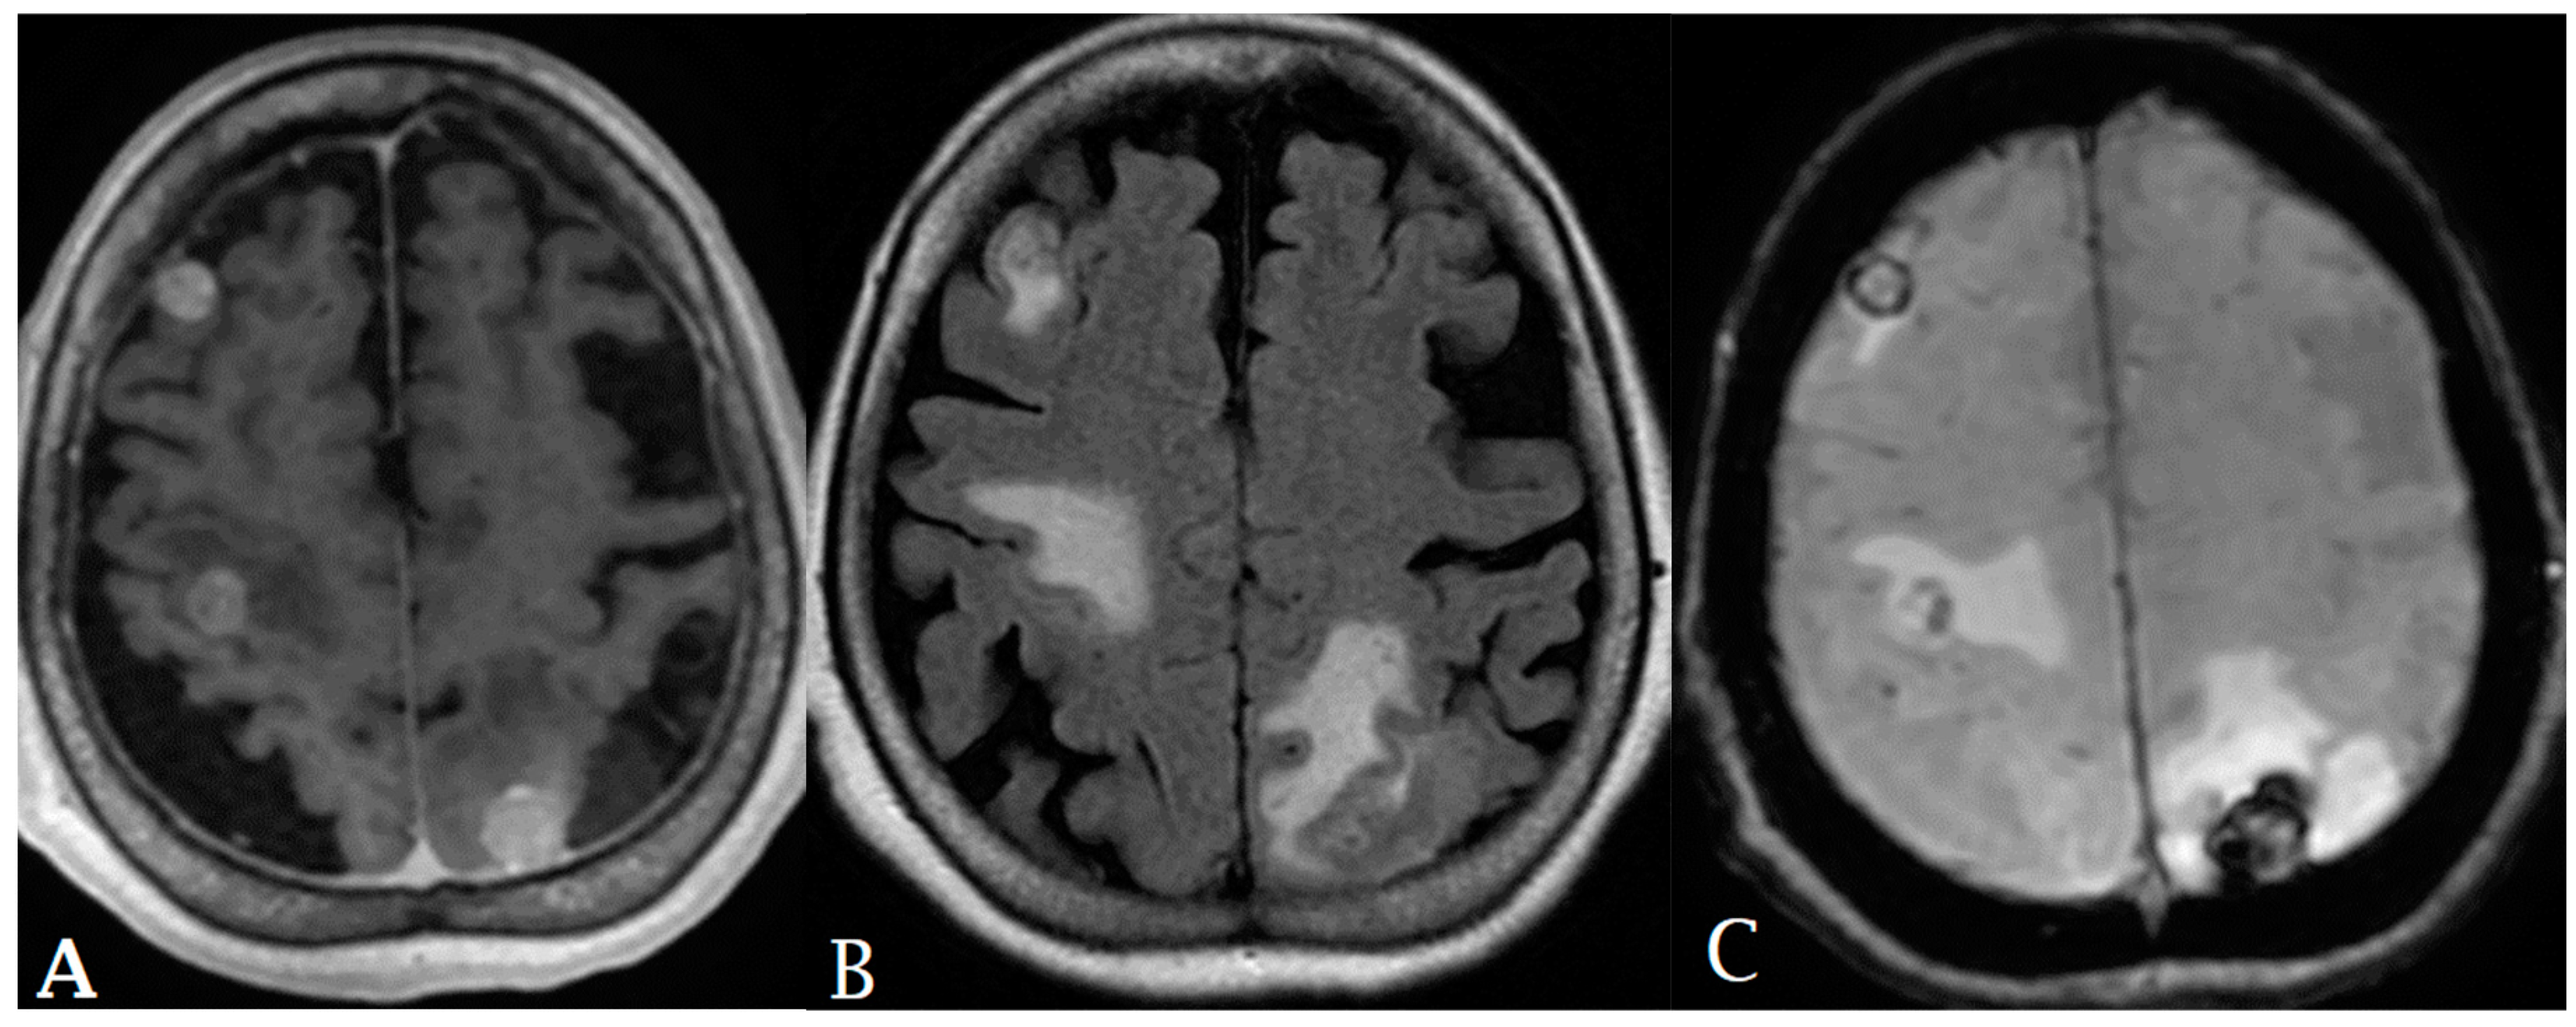

- Priya, S.; Liu, Y.; Ward, C.; Le, N.H.; Soni, N.; Pillenahalli Maheshwarappa, R.; Monga, V.; Zhang, H.; Sonka, M.; Bathla, G. Radiomic Based Machine Learning Performance for a Three Class Problem in Neuro-Oncology: Time to Test the Waters? Cancers 2021, 13, 2568. [Google Scholar] [CrossRef]

- Bathla, G.; Dhruba, D.D.; Soni, N.; Liu, Y.; Larson, N.B.; Kassmeyer, A.B.; Mohan, S.; Roberts-Wolfe, D.; Rathore, S.; Le, N.H.; et al. AI-based classification of three common malignant tumors in neuro-oncology: A multi-institutional comparison of machine learning and deep learning methods. J. Neuroradiol. 2023. [Google Scholar] [CrossRef] [PubMed]

- Kniep, H.C.; Madesta, F.; Schneider, T.; Hanning, U.; Schönfeld, M.H.; Schön, G.; Fiehler, J.; Gauer, T.; Werner, R.; Gellissen, S. Radiomics of Brain MRI: Utility in Prediction of Metastatic Tumor Type. Radiology 2019, 290, 479–487. [Google Scholar] [CrossRef] [PubMed]

- Ortiz-Ramón, R.; Larroza, A.; Ruiz-España, S.; Arana, E.; Moratal, D. Classifying brain metastases by their primary site of origin using a radiomics approach based on texture analysis: A feasibility study. Eur. Radiol. 2018, 28, 4514–4523. [Google Scholar] [CrossRef] [PubMed]